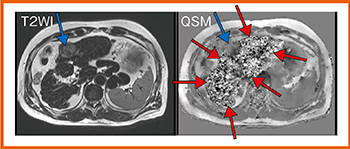

腹部QSMでは,肺や腸管の空気によるB0不均一,皮下や臓器周囲の脂肪,体動などが問題となる。従来のQSM解析では,局所磁場マップから直に解析するため,水と脂肪の境界に強いアーチファクトが生じていた。日立のQSMは,局所磁場マップから水画像と脂肪画像を作成した上でQSM解析を行い,解析結果を統合する。そのため腹部でも,息止め可能な撮像時間(19秒)で,アーチファクトのない画像を取得することができる11)。

当院では現在,さまざまな症例を対象に腹部QSMの検討を行っている。肝硬変(LC)+肝細胞がん(HCC)の症例(図6)のQSMでは,背景肝の磁化率が不均一であることが明瞭にわかる。白い部分はLCに伴う鉄沈着であると考えられる。

腹部QSMとChild-Pughスコアの対比では相関は明らかになっていないが,肝内の磁化率の分散についてコントロール群とLC群を比較したところ,LC群では分散が非常に大きくなることがわかった。

また,超音波エラストフラフィとQSMを比較したところ,エラストグラフィの弾性率と肝内磁化率の分散に正の相関が認められたことから,LCの診断にQSMが応用できる可能性があると考える。

図6 腹部QSM:LC+HCC